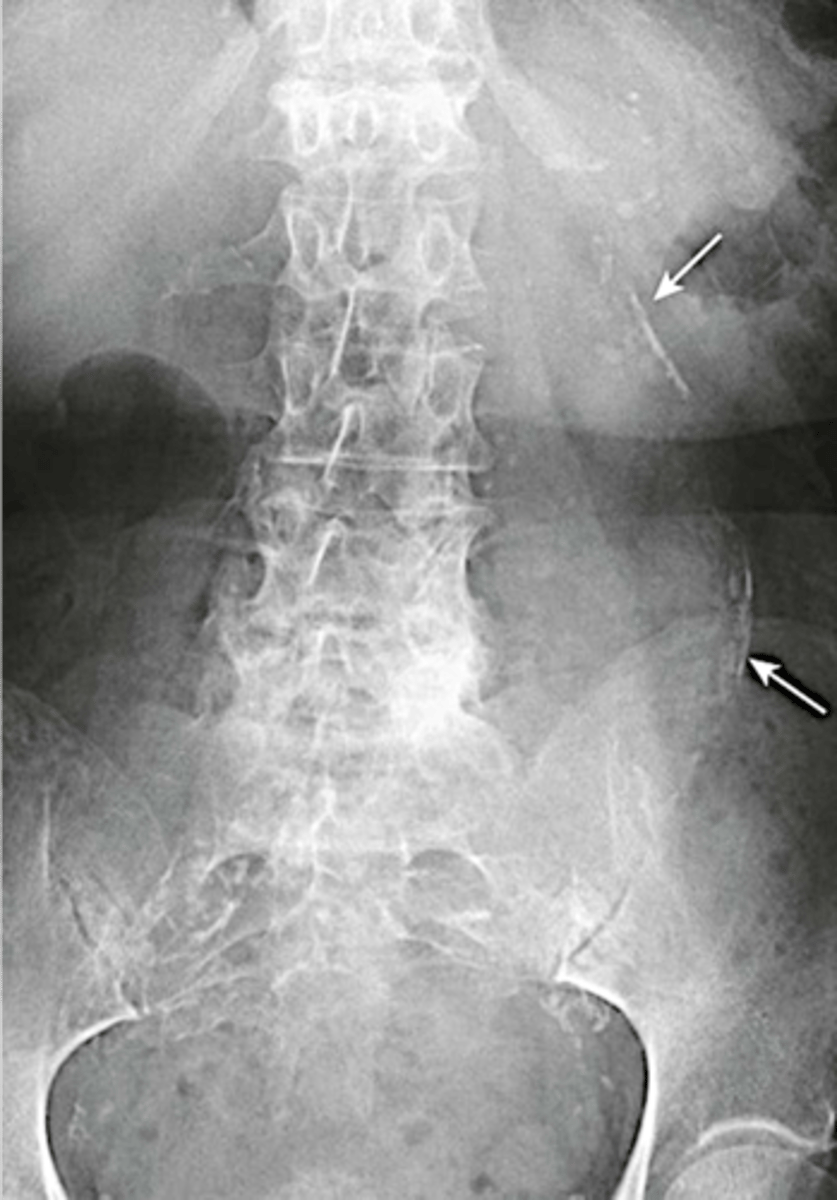

Abdominal aortic aneurysm calcification

Abdominal aortic aneurysm calcification (pic 2)

Abdominal aortic aneurysm calcification (pic 3)